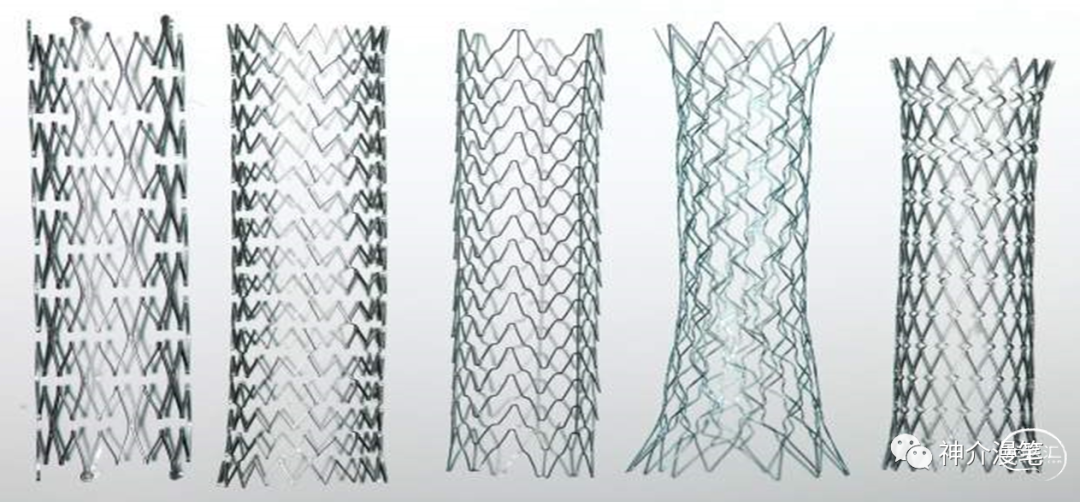

90年中后期,支架设计的春天来临,不锈钢材质被舍弃,新一代镍钛合金材质自膨支架开始大杀四方。涌现了大量的开环,闭环,复合设计等特点的支架。并且随着球囊,指引导管,保护伞的组合开始挑战CEA的江湖地位

第一个概念:开环支架与闭环支架。开环支架有自己独立的支架单元,每个单元之间有少数几个连接点相连,这样能保证每一个支架单元的相对独立性。在弯曲迂曲,管径差异较大的血管条件下能保持更好的贴壁性。下图即为典型的开环支架设计,红色部分为支架单元之间的连接点,其余部分呈现为开放不连续状态。

闭环支架的设计特点和开环支架刚好相反,所有的支架单元都呈现出连续封闭的状态,整个支架为一个连续完成的整体。其设计的特点使得其网眼更小,更利于提高局部金属覆盖率与对斑块的保护。但是其在迂曲血管的贴壁性会略差,同时因为其作为一个整体存在的特点,其趋势是使血管变直。因此对于血管走形的改变会略大。下图为闭环支架的设计特点,可以看到所有支架网格均为封闭连续的结构。

编织支架在不同管腔内会拉伸,并有释放后短缩现象。雕刻支架:金属圆筒由激光镂空雕刻形成,雕刻支架长度基本稳定,拉伸或短缩的现象极为少见。从结构特点上我们能知道,开环支架全部是雕刻支架,闭环则可能是雕刻也可能是编织。看过我这篇小豆腐块的同志,千万不要再从你们嘴里出现编织开环支架这个词了。下面第一个图,编织闭环支架,第二图为激光雕刻开环支架。

第三个概念:普通支架与锥形支架。

锥形支架:支架头尾端直径不一致。这个其实很好理解,锥形支架更为适合管腔直径差距较大的靶血管

下面第一个图,普通支架,第二图为锥形支架。

简要的几款主流颈动脉支架的汇总图